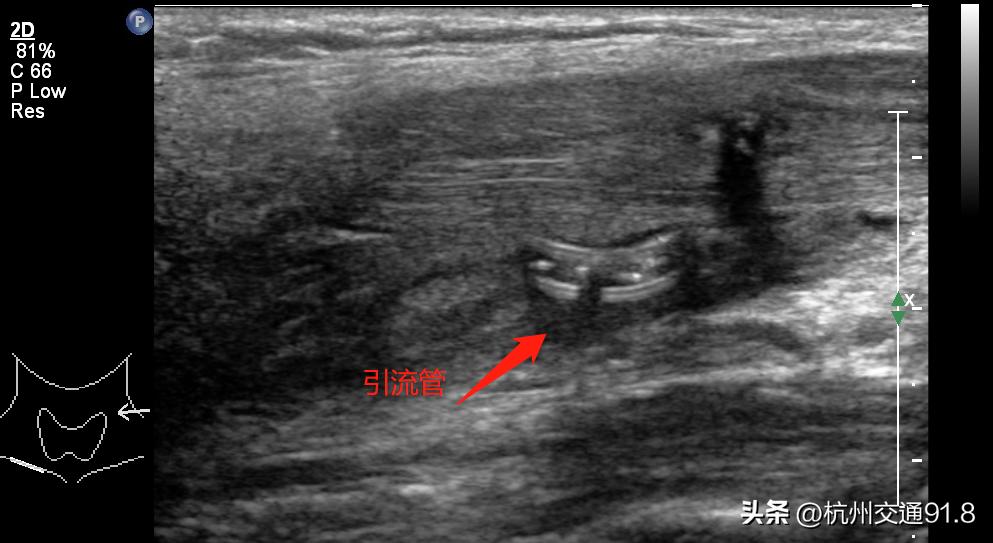

多学科联合会诊后,迅速制定了治疗方案,张主任为小李进行了超声引导下放置引流管引流脓液,并结合抗生素抗感染治疗。

超声引导下置入引流管